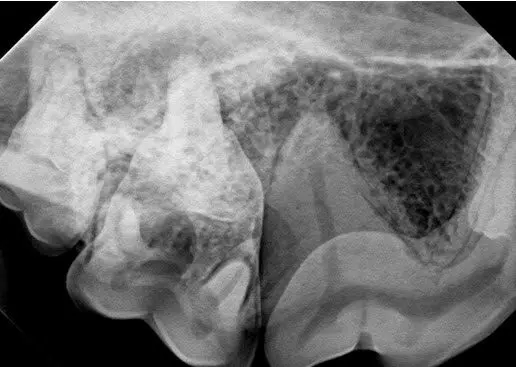

Radiograph of the teeth on the right side, pictured above.

Large periapical lucencies are seen around the palatal (upper group of arrows) and distal (lower group of arrows) roots of 109. The large distal root of 108 appears to be normal in this view. Views showing the mesio-buccal and palatal roots of 108 were also normal. The PAL surrounding the distal root of 109 likely extends to the mesial root of 110.

While 108 has a small uncomplicated crown fracture, the tooth appears vital at this time. The root canals of 108 and 208 are both of similar size and the periodontal ligament space (pdl) is visible around the distal root of 108. The uncomplicated crown fracture of 108 should be treated with bonded sealants at this time, with follow-up radiographs of that tooth being taken in 6-12 months to ensure that the tooth remains vital. For more information on the potential ramifications of small cusp tip fractures, click this link to see a past newsletter on this topic: fractured teeth